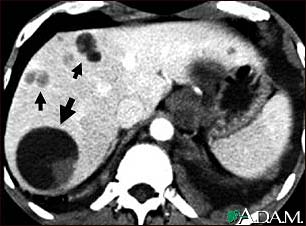

Liver echinococcus - CT scan

This upper abdominal CT scan shows multiple cysts in the liver, caused by dog tapeworm (echinococcus). Note the large circular cyst (seen on the left side of the screen) and multiple smaller cysts throughout the liver.